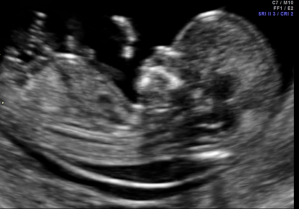

Nabízíme ultrazvuková vyšetření plodu sloužící k záchytu vrozených vývojových vad a chromozomálních poruch. Patří mezi ně prvotrimestrální kombinovaný screening v 11.-14. týdnu těhotenství a screening preeklampsie, kdy se kombinuje specializované ultrazvukové vyšetření plodu a odběr krve na biochemické markery. Dále ve druhém trimestru specializované ultrazvukové vyšetření plodu v 20.-22. týdnu včetně podrobného ultrazvukového vyšetření srdce plodu a konečně ultrazvukové vyšetření v 30. týdnu.